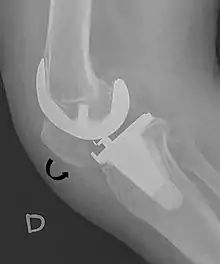

- ↑ Melloni, Pietro; Veintemillas, Maite; Marin, Anna; Valls, Rafael (2013). "Imaging Patellar Complications After Knee Arthroplasty". Arthroplasty - Update. doi:10.5772/53666. ISBN 978-953-51-0995-2. (CC-BY-3.0)

A patella alta is a high-riding (superiorly aligned) patella. An attenuated patella alta is an unusually small patella that develops out of and above the joint.

A patella baja is a low-riding patella. A long-standing patella baja may result in extensor dysfunction.[5]

The Insall-Salvati ratio helps to indicate patella baja on lateral X-rays, and is calculated as the patellar tendon length divided by the patellar bone length. An Insall-Salvati ratio of < 0.8 indicates patella baja.[6]